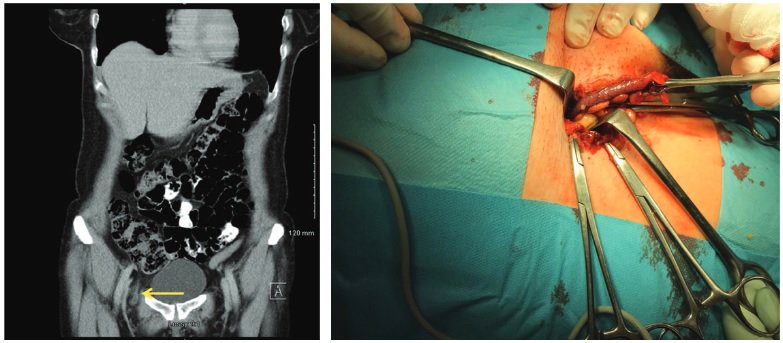

Diverticulitis is common and increasing in frequency. Most cases are uncomplicated and are typically treated with antibiotics. Sigmoid resection is performed in cases of severe disease and is considered on an individual basis in patients with recurrences. nej.md/2yqYBuv